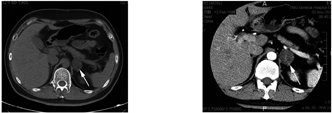

入院后血、尿、便常规,凝血常规,肝、肾功能,空腹血糖,游离甲功均未见异常。电解质:血钙2.25 mmol/L(参考值2.15~2.55 mmol/L),24 h尿钙11.07 mmol/24 h(参考值2.50~7.50 mmol/24 h),余未见异常。血脂:总胆固醇5.35 mmol/L(参考值3.59~5.17 mmol/L),低密度脂蛋白-胆固醇3.61 mmol/L(参考值1.33~3.36 mmol/L)。骨代谢指标:25羟维生素D 52.85 nmol/L(参考值15.50~113.75 nmol/L),甲状旁腺素3.66 pg/ml(参考值1.10~7.30 pg/ml)。24 h尿皮质醇159.84 μg/24 h(参考值30.00~110.00 μg/24 h);皮质醇昼夜节律消失且1 mg过夜地塞米松抑制试验(DST)未被抑制(表2)。术前性激素相关指标见表3。垂体MRI平扫:垂体形态正常,冠状位正中高度约4 mm,垂体信号未见明显异常;垂体柄居中,无增粗。肾上腺CT增强:左侧肾上腺区可见类圆形肿块,直径约31 mm,中心可见片状不规则低密度区,增强检查肿块呈不均匀强化(图1),强化各期CT值约38、69、46、32、38 HU,考虑左侧肾上腺腺瘤;右侧肾上腺形态、大小及密度未见异常,增强后未见异常强化。胸部CT平扫:两肺间质纹理增多;两肺下叶背侧多发片状磨玻璃样密度影伴细索条影,考虑慢性炎症。心脏彩色多普勒:未见明显异常。腹部超声:肝、胆、胰、脾及双肾未见明显异常。泌尿系超声:右侧睾丸大小约3.3 cm×2.2 cm×1.8 cm,形态正常,右侧精索静脉曲张;左侧阴囊空虚。骨密度(Z值):腰椎L1:-1.3;腰椎L2:-1.6;腰椎L3:-1.4;腰椎L4:-1.6;腰椎L1~L4总Z值-1.5;髋关节:股骨颈:-1.6;Wards三角:-2.5;全髋:-2.4。染色体G带(400条带)核型分析结果:46,XY。临床考虑诊断为:亚临床库欣综合征(SCS)、左侧肾上腺肿物(性质待查)、骨质疏松、高促性腺激素性性腺功能减退症。